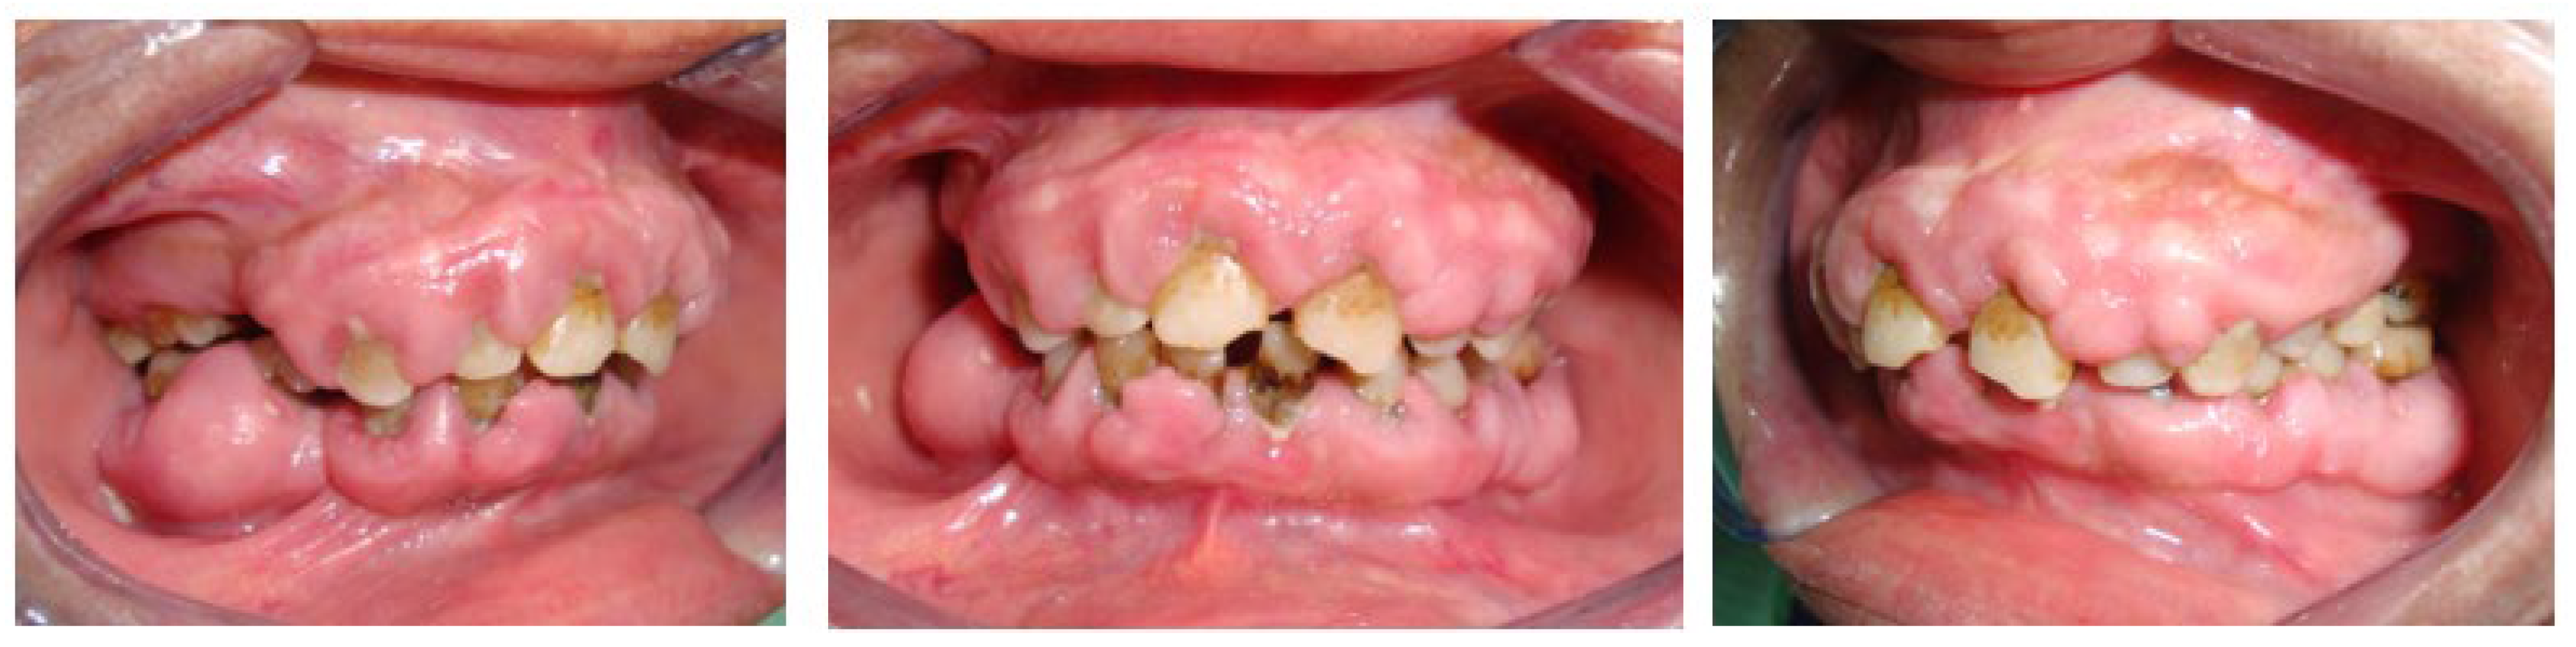

The intraoral examination revealed generalized marginal gingival inflammation, plaque and calculus accumulation, and attachment loss ranging from 3 to 10 mm. Additionally, the patient exhibited a firm, pale-pink, shiny, and smooth hyperplastic type of generalized gingival growth that covered almost all the teeth without causing pain (Figure 2).

Figure 2. Generalized marginal gingival inflammation, accumulation of plaque and calculus, generalized gingival growth, hyperplastic type, firm consistency, pale-pink, shiny and smooth in appearance, painless and pedicled covering almost all the teeth.